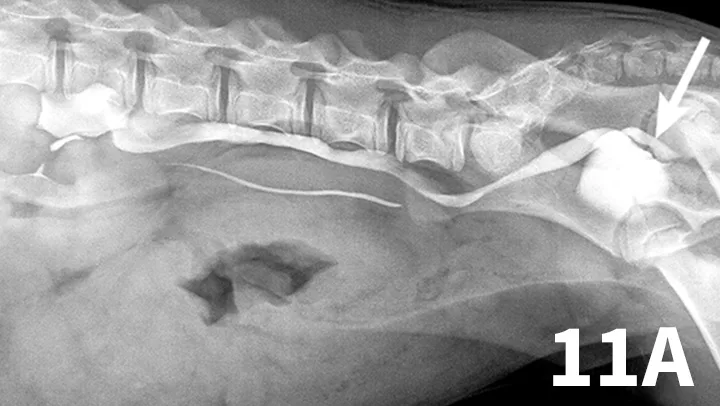

Figure 11A.

Lateral oblique view from a young dog with a left ectopic ureter that was diagnosed with excretory urography. The left ureter and renal pelvis are dilated. The left ureter extends beyond the trigone region of the urinary bladder on the lateral oblique view (arrow).